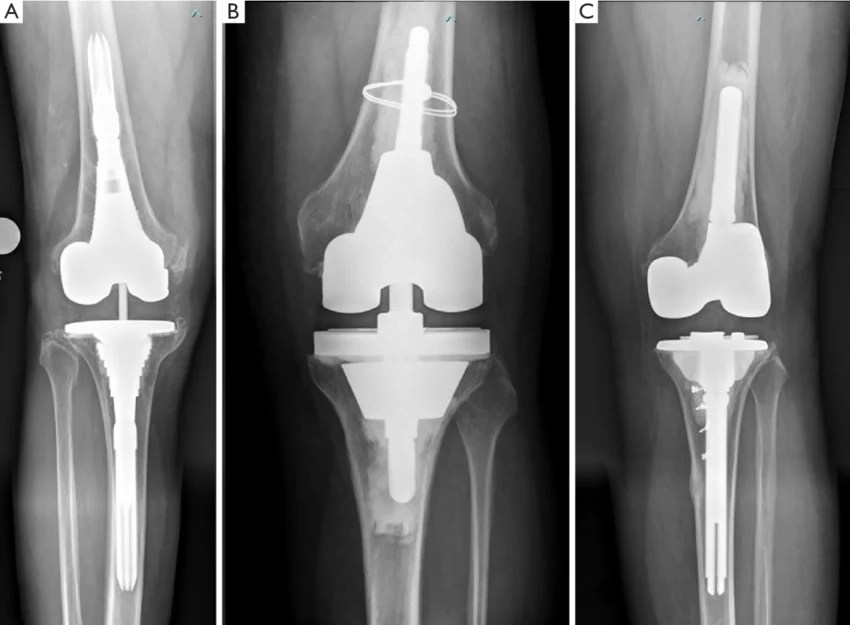

Creating a dual articulating antibiotic spacer for management of an Alternative Knee Replacement Surgery Unispacer The unispacer (zimmer, inc., warsaw, in) is a metallic tibial hemiarthroplasty for treatment of isolated osteoarthritis of the medial compartment of the joint. The unispacer™ knee implant enhances knee function in the treatment of isolated tibiofemoral osteoarthritis graded 2. 4.5/5 (36) 4.5/5 (36) It requires no bone cuts or. Given its low cost and simplicity of insertion, the. Alternative Knee Replacement Surgery Unispacer.